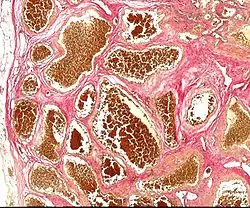

| Histology of a cavernous hemangioma | |

Cerebral cavernous malformation (CCM) is a cavernous hemangioma that arises in the central nervous system. It can be considered to be a variant of hemangioma, and is characterized by grossly large dilated blood vessels and large vascular channels, less well circumscribed, and more involved with deep structures, with a single layer of endothelium and an absence of neuronal tissue within the lesions. These thinly walled vessels resemble sinusoidal cavities filled with stagnant blood. Blood vessels in patients with cerebral cavernous malformations (CCM) can range from a few millimeters to several centimeters in diameter. Most lesions occur in the brain, but any organ may be involved.[1]